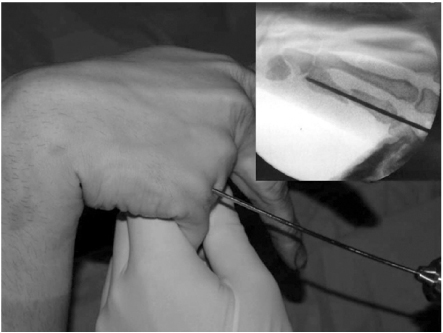

The surgery was performed under general or regional anesthesia with image intensification, preferably with a tourniquet on the upper arm. Under the fluoroscopy, closed reduction of the metacarpal fracture was achieved by manipulation, and 1.6 mm K-wire was inserted from metacarpal head with MP joint flexion for easy access to the medullary canal (Fig. 1). When the wire tip passed fracture site and reach to metacarpal base, wrist was bent maximum and further penetration was performed to proximal area (Fig. 2). The distal end of K-wire was pulled up until its tip end lay within the metacarpal head (Fig. 3). Penetrated proximal part of wire was bent over, cut and buried under the skin (Fig. 4). During this procedure, any rotation of fracture was carefully checked with passive flexion and extension motion of the finger. Ulnar gutter splint was applied for rotational stability and pain relief. It was changed to extension block splint and encouraged motion exercise from postoperatively 1 week. After fracture healing, the wire was removed with local anesthesia in the outpatient department in all cases. We make small skin incision at proximal bended wire and pull out that with local anesthesia.

Fig. 2

When the wire tip passes fracture site and reaches to metacarpal base, wrist is bent maximum and further penetration is performed to proximal area.

Fig. 2 When the wire tip passes fracture site and reaches to metacarpal base, wrist is bent maximum and further penetration is performed to proximal area.